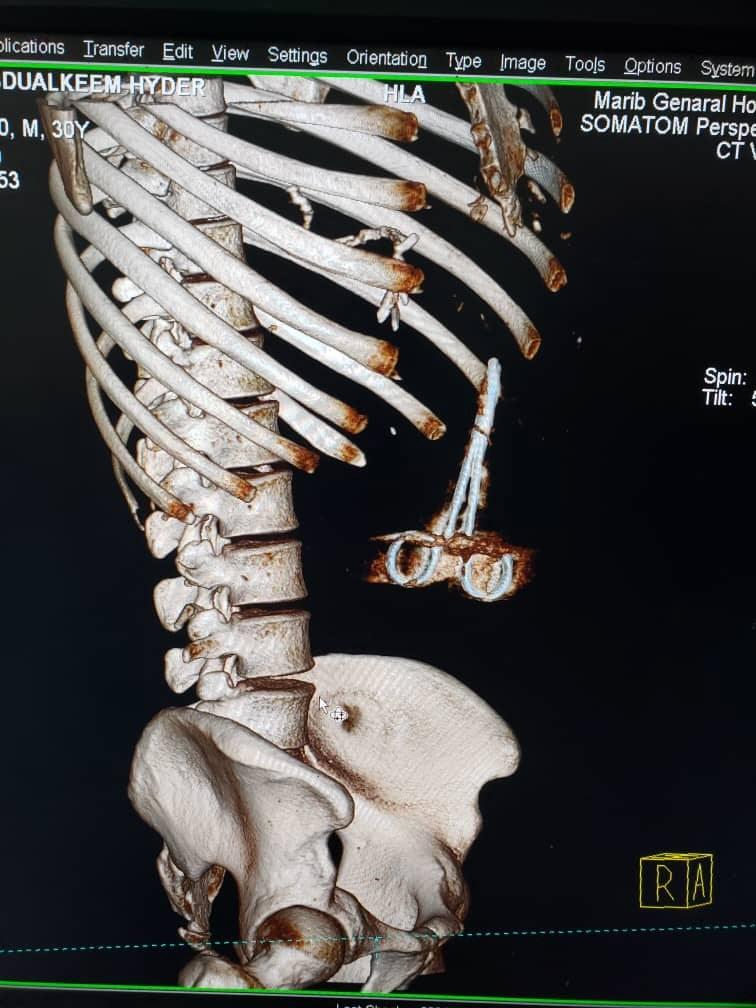

وأثيرت قضية الخطأ الطبي بعد ظهور "مقص" في أشعة مقطعية أجراها الجريح "حيدر"، بعد شعوره المتكرر بألم حاد ومتقطع في منطقة الصدر، ليتفاجأ بالخطأ الكارثي الذي وقع فيه جراحو هيئة مستشفى مأرب، أثناء إجراء عملية جراحية له.

الاشعة المقطعية تظهر المقص داخل جسم الجريح

الأشعة المقطعية تظهر المقص داخل جسم الجريح